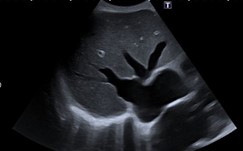

Gallenblase

Darstellung und Identifikation im B-Bild

Pathologien der Gallenblase

| 13:15 - 15:00 | Gallenwege, Gallenblase, Pankreas |